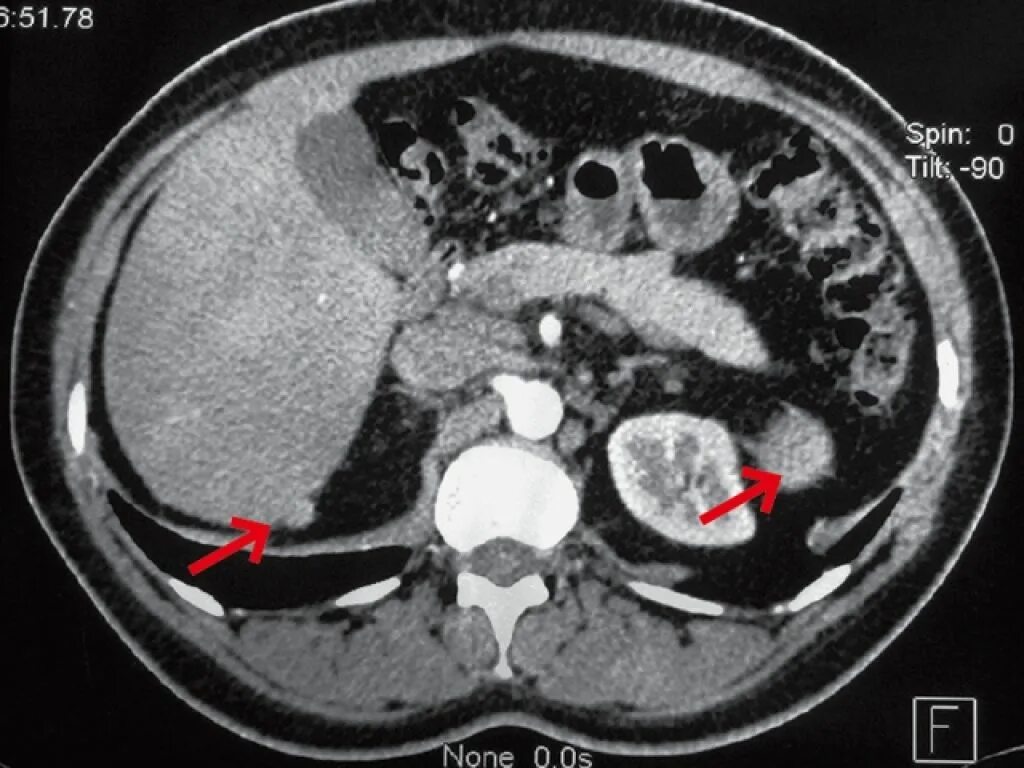

Забрюшинная онкология